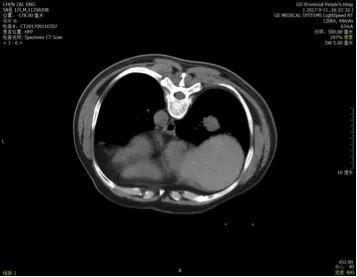

5. 2017-9-5广东省人民医院PET提示:右肺下叶肿物2.8*2.7cm,SUV 22.3,双侧颈部、双侧气管旁、隆突下、食管旁、右侧肺门淋巴结肿大,代谢升高,考虑为转移灶,右侧肾上腺转移灶,具体结果见下图:

(准备行经皮肺穿刺活检时图像)